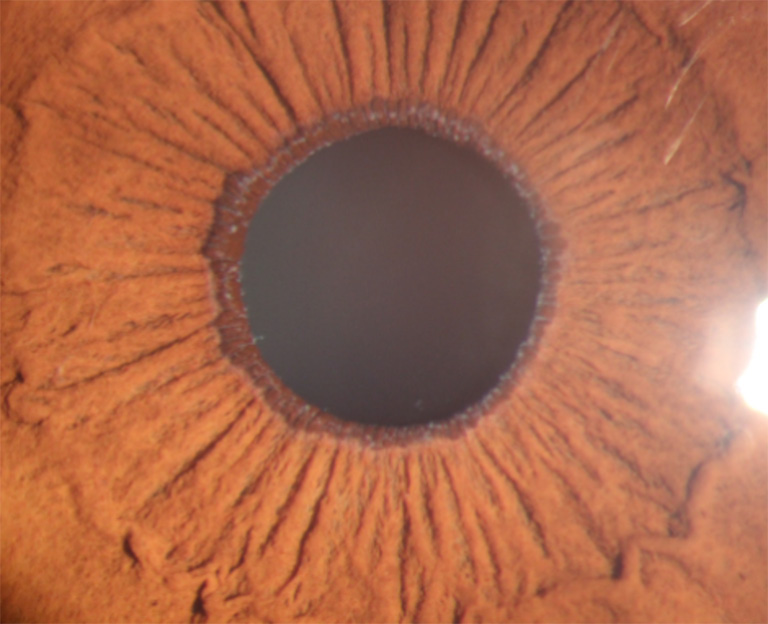

图1 病例1:散瞳前可见瞳孔缘灰白色碎屑样物质沉积

Figure 1 Case 1: deposits of white material on the pupillary border of the iris before pupillary dilation

患者,男,60岁,因右眼胀痛伴视力下降4个月,于西安市第四医院眼科就诊。眼部检查:右眼视力0.5,左眼视力0.8,右眼眼压50.3 mmHg(1 mmHg=0.133 kPa),左眼眼压14.6 mmHg。右眼结膜轻度充血,角膜未见水肿,角膜后沉着物(-),前房深度正常,房水闪辉(+),虹膜纹理清晰,瞳孔圆,直径约4 mm,对光反射迟钝,瞳孔缘可见灰白色碎屑样物质沉积(图 1),晶状体轻度混浊,散大瞳孔后可见晶状体前囊周边部环状灰白色颗粒混浊带(图 2),眼底视盘边界清,色淡白,杯盘比(C/D)约0.8,视网膜平伏,黄斑中心凹反光不清。左眼检查未见明显异常。患者既往体健。房角镜检查:双眼宽角,右眼房角可见较多大小不等色素颗粒沉着,跨越Schwalbe线,形成Sampaolesi线,色素III级,左眼色素I~II级(图 3)。Humphrey视野:右眼管状视野,左眼未见异常(图 4)。光学相干断层扫描(optical coherence tomography,OCT)检查:右眼视盘周围视网膜视神经纤维层厚度明显变薄(图 5)。诊断:1 )右眼剥脱性青光眼,2 )双眼年龄相关性白内障。给予右眼溴莫尼定滴眼液3次/ d、布林佐胺滴眼液3次/ d、噻吗洛尔滴眼液2次/ d联合甘露醇注射液静脉滴注降眼压治疗,完善术前检查排除手术禁忌证后,局部麻醉下行右眼复合式小梁切除术。术后第1天右眼视力0.4,眼压11.5 mmHg,上方结膜滤过泡隆起弥散,角膜透明,角膜后沉着物(-),前房中深,房水闪辉(+),瞳孔圆,直径4 mm,对光反射迟钝,瞳孔缘可见灰白色碎屑,虹膜周切口通畅,晶状体轻度混浊,眼底检查同前。术后1周右眼视力0.5,眼压15.8 mmHg;术后3个月,右眼视力0.5,眼压波动于15~18 mmHg,应用噻吗洛尔滴眼液,眼压波动于10~12 mmHg,滤过泡平坦,余检查大致同前。

XFG双眼发病时间和程度可以不对称,双眼发病者的年龄比单眼患者高,在所有单眼患者的对侧眼球结膜中均可发现剥脱样纤维物质存在。灰白色头皮屑样剥脱物质可沉积在瞳孔缘、晶状体前囊、角膜内皮、虹膜、前房角、睫状体带和玻璃体前界膜等处[6]。虹膜改变是本病早期易于发现的体征,32%~39%的患眼中可见到瞳孔缘头皮屑样剥脱物质沉着。晶状体前囊剥脱物质分布典型者表现为3个区域:1)中央盘(瞳孔区),为半透明绒毛状的中央盘形,出现率为80%,散瞳后尤为明显,可暴露盘形区的边缘部,呈薄片状;2 )中间透明带,位于中央盘形区与周边颗粒带之间,因剥脱物质被虹膜活动擦除而保持透明;3 )周边颗粒带,呈锯齿状或花边样灰白色颗粒样混浊环带,为本病的主要诊断依据。小梁网色素沉着增多早于瞳孔缘或晶状体前囊剥脱物质的出现。

本文报告的2例患者右眼瞳孔缘均可见典型灰白色碎屑样物质沉着,散瞳检查发现晶状体前囊周边颗粒带,房角镜检查小梁网广泛不均匀色素沉积,可见Sampaolesi线,患者眼压高,管状视野,故XFG诊断明确。治疗主要有药物、激光和手术。药物治疗同原发性开角型青光眼,但药物治疗效果相对较差[7]。散瞳可加重剥脱物质的数量及剥脱物质进入房角阻塞小梁网,所以慎用散瞳剂。氩激光小梁成形术早期降眼压效果理想,但术后炎症反应重,降眼压效果随时间逐渐下降,3~6年内降至35%~55%,远期效果较原发性开角型青光眼差。对于闭角型XFG患者,由于悬韧带异常晶状体前移,治疗上以摘除晶状体为主。XFG患者就诊时眼底及视野损害均较重,对降眼压药物反应差,病程进展快,多数患者需手术干预。本文2例患者就诊时已是晚期青光眼,眼压高,管状视野,因此选择手术治疗。